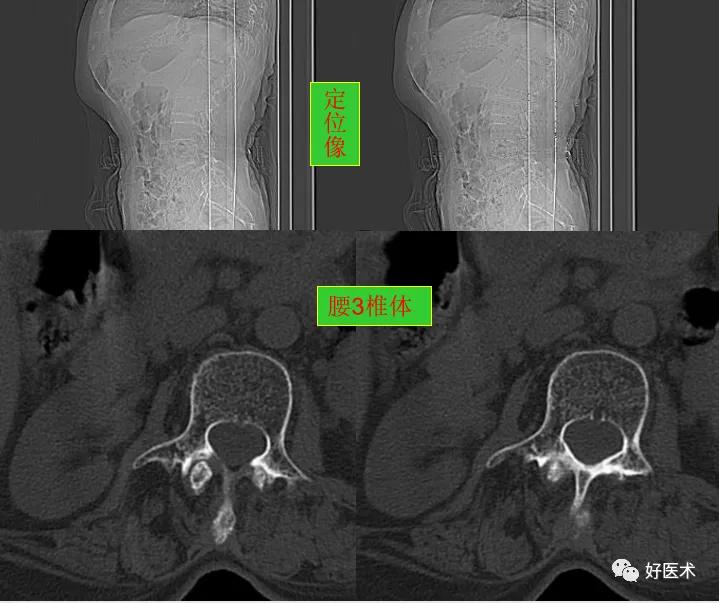

CT图像,腰椎常规采用序列扫描,腰椎体2层,腰间盘4层,层厚2.5mm,一般扫描范围包括腰2--骶1椎体及所属间盘。

腰椎曲度稍变直, 骨质轻度增生,胸12椎体陈旧压缩性骨折。

腰4、5椎体及附件骨质未见著变。